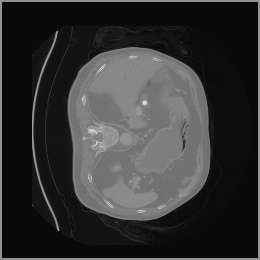

As shown in Figure 5, the generated slices exhibit high consistency across adjacent slices. The anatomical structures and semantic patterns are smoothly and coherently preserved between slices, indicating that our model is capable of generating 3D-consistent synthetic images rather than isolated 2D slices.

To demonstrate the advantages of 3D semantic image synthesis over 2D semantic semantic image synthesis, we conducted a detailed comparison with the SegGuidedDiff [26] model. SegGuidedDiff generates medical images based on 2D semantic maps, producing individual 2D slices that are later stacked to form a 3D image. However, this approach has limitations in capturing spatial continuity and coherence across slices, which is critical for representing the spatial structure of 3D medical images. As a result, inconsistencies often arise between different slices, particularly in preserving anatomical structures across the coronal and sagittal planes. The generated images exhibit varying levels of denoising, resulting in differences in brightness and sharpness across the images. This inconsistency in denoising can lead to noticeable variations in visual quality, where some regions appear clearer and others less distinct.

In our approach, we employ a compression factor of 4 to encode 3D medical images into the latent space. This level of compression reduces the spatial resolution of the original image (e.g., from 256×256 to 64×64 per slice), while still preserving the essential anatomical structures and semantic content. The latent representation at this scale offers a favorable trade-off between dimensionality reduction and semantic fidelity. Specifically, although fine-grained textures are simplified, key structural patterns (e.g., organ boundaries, lesion shapes) remain visually distinguishable and semantically coherent. As the compression rate increases, the latent representations become progressively more abstract. With lower compression (e.g., 2× or 4×), the latent features preserve key anatomical structures and spatial layouts, making them beneficial for our semantic image synthesis task in latent space, as the model can operate on compressed representations that retain sufficient semantic information without being overwhelmed by high-frequency noise. In contrast, higher compression rates (e.g., 8× or above) lead to a loss of fine-grained details and reduced semantic fidelity. The choice of a 4× compression thus ensures that the latent features are compact and meaningful, facilitating effective conditional generation while significantly reducing computational overhead. We therefore adopt a 4× compression as a compromise between computational efficiency and semantic preservation. The corresponding 2D slices in image space and latent space are shown in Figure 7.

Figure 8 further supports these findings: the images generated by Med-LSDM preserve spatial coherence across coronal and sagittal planes, whereas those from SegGuidedDiff show noticeable inconsistencies. These artifacts likely result from the 2D nature of SegGuidedDiff, which fails to account for 3D spatial relationships. In contrast, our model’s volumetric diffusion framework inherently preserves anatomical consistency, highlighting its advanta in synthesizing high-fidelity 3D medical images.